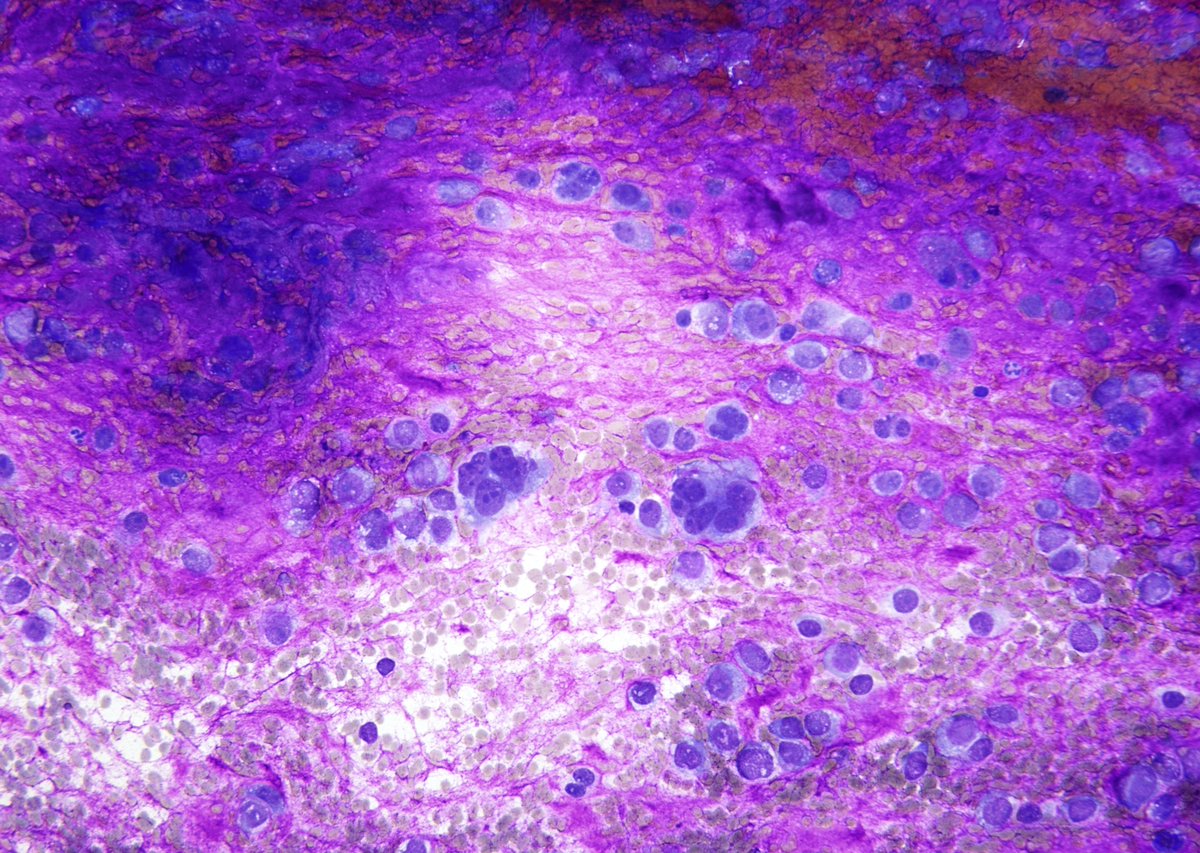

Hepatoblastoma, mixed epithelial and mesenchymal type: 🔸 Most <5yo 🔸 Epithelial (resemble immature hepatocytes) and mesenchymal (spindled) components 🔸 Nuclear β-catenin+ (80% cases) in both components #FNAFriday #CytoPath #liverpath #GIpath #pedipath #Pathology PathSpotters

Hepatoblastoma, mixed epithelial and mesenchymal type:

🔸 Most &lt;5yo

🔸 Epithelial (resemble immature hepatocytes) and mesenchymal (spindled) components

🔸 Nuclear β-catenin+ (80% cases) in both components

#FNAFriday #CytoPath #liverpath #GIpath #pedipath #Pathology <a href="/PathSpotters/">PathSpotters</a>